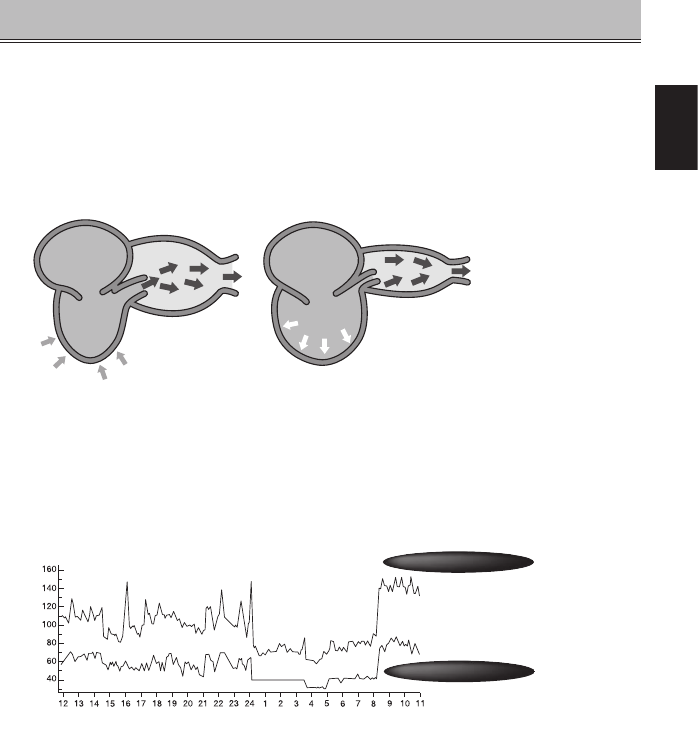

The heart is a pump that circulates blood throughout your body. Blood is pumped from the

heart at a constant pressure into arteries. This pressure is called the arterial blood pressure

and represents, in general terms, your blood pressure. Blood pressure is indicated by several

kinds of pressures, including the systolic pressure that occurs when the heart pumps blood

and the diastolic pressure that occurs when blood returns to the heart.

(Systolic)

(Diastolic)

Artery Artery

Left atrium

Left

ventricle

Left atrium

Left

ventricle

Dilation

The artery wall expands.

Contraction

Normal state is restored

Your blood pressure changes all the time.

Your blood pressure differs according to your age, gender and a range of other factors. It is

likely to be affected by your biorhythm during the day and by your posture, physical activities,

mental activities, level of stress and even by the air temperature. The blood pressure of a

healthy person generally varies within a day.

Blood pressure value (mmHg)

Time of day

Systolic blood pressure

Diastolic blood pressure